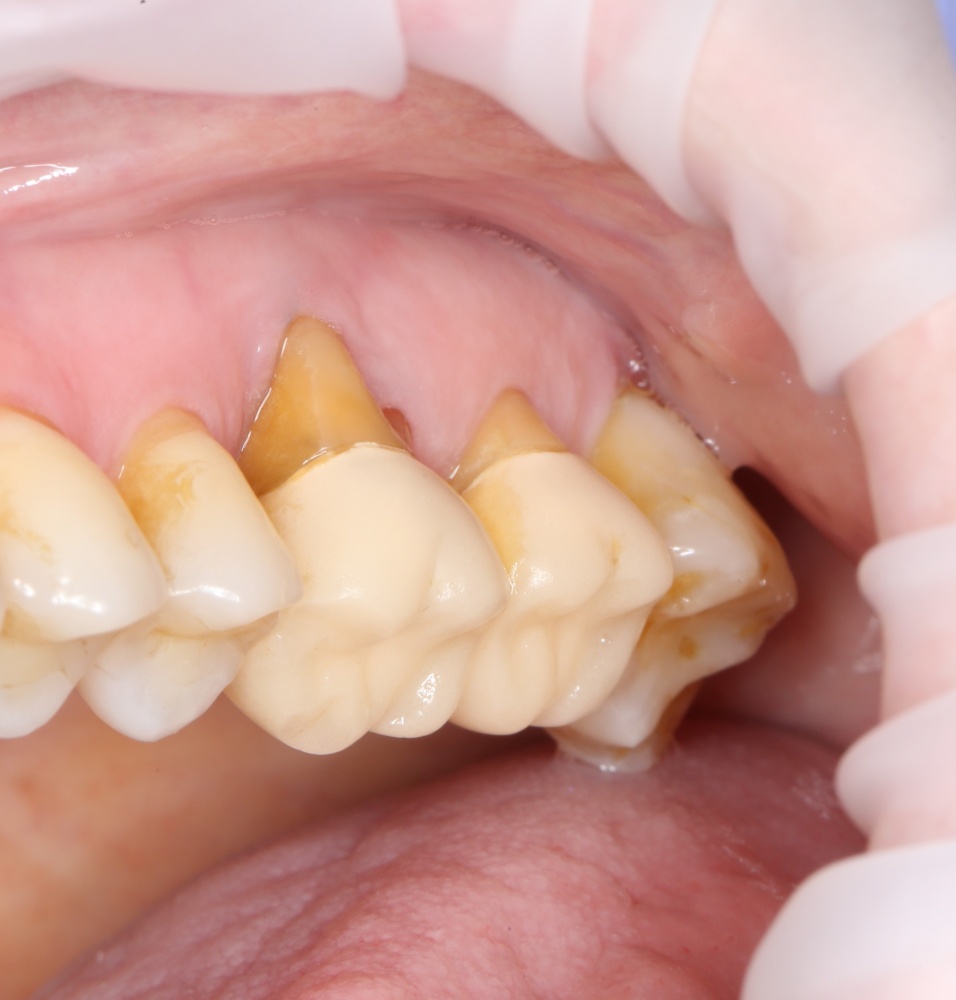

Простой синуслифтинг. Часть I.